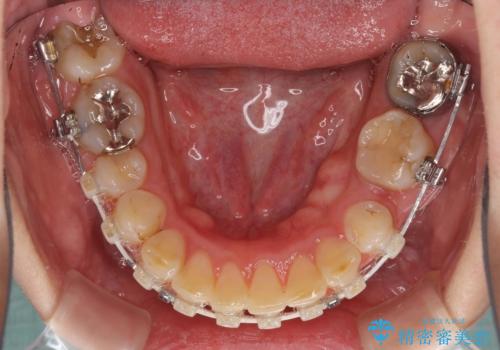

- 矯正装置

- ハーフリンガル

口元の突出感はあまり気になっていませんでしたが、上下の前歯の前後差が大きかったため、上顎左右の第一小臼歯を抜歯し、上顎が裏側装置であるハーフリンガルにて矯正治療を行うこととしました。

咬合力が非常に強く、スペースがなかなか閉じなかったことと、上下の正中が著しくずれてきてしまったため、下顎左側小臼歯を途中抜歯することとなりました。